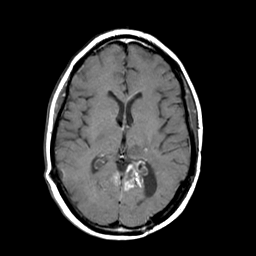

MR Study #3 -- Slice #29